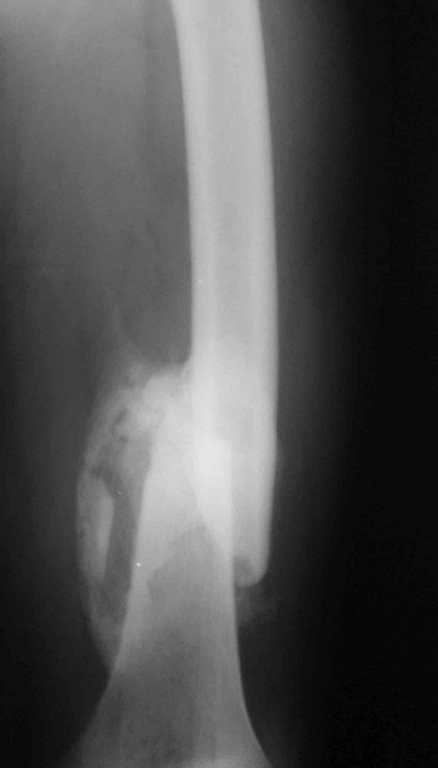

Re: 32- летний пациент с переломами обоих бедер после неудачного оперативного и консервативного лечения.

Иллюстрации к сообщению

б) Наложить параллельно аппарат внешней фиксации на второе бедро, выполнить дистракцию в течении 10-ти дней, после чего произвести замену метода на погружной остеосинтез пластиной. Желательно чтобы ноги были одинаковой длины. ЛФК с первого дня после операции.

Cyдя по представленным рентгенограммам оба бедра консолидированы. Необходима активная разработка движений в коленных суставах. Хотелось бы увидеть фотоснимки больного ( нижних конечностей спереди и сбоку). Если стержень мешает разработке движений то его надо удалить.

О происхождении такого запущенного случая- мой коллега работает экспертом ВТЭК и тянет в отделении и не такие казусы. Сегодня была сделана операция удален стержень из бедра и установлен стержневой аппарат из 2 опор, слева подвижности не наблюдалось, продолжается ЛФК. При необходимости позднее будет выполнена надмыщелковая корригирующая остеотомия. Спасибо всем за советы.